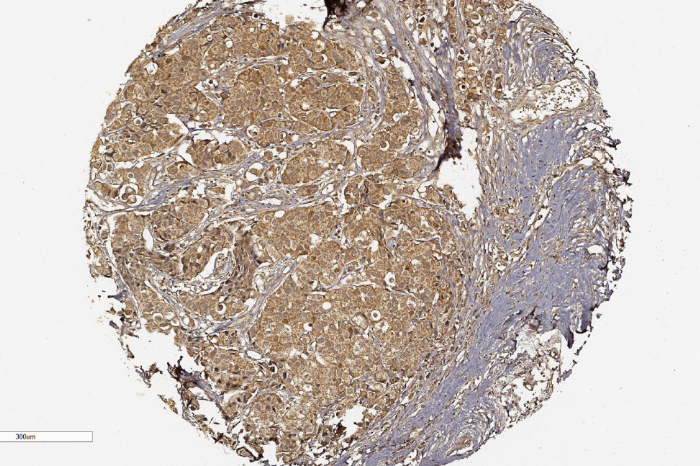

Foto: EFE